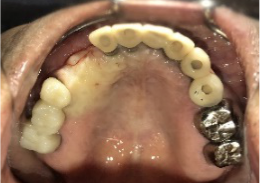

女性Mさん 40代(インプラント)

主訴

下、左右歯がないところに歯を入れたい。

治療内容

右下に2本、左下に1本インプラントを入れました。

所感

下顎左右奥の歯がないところに、インプラント治療を希望されて来院されました。X-Guideを使用し埋入しました。治療後「左右の奥歯でしっかり噛めてうれしいです。」と、とても喜んでくださいました。

Before

After